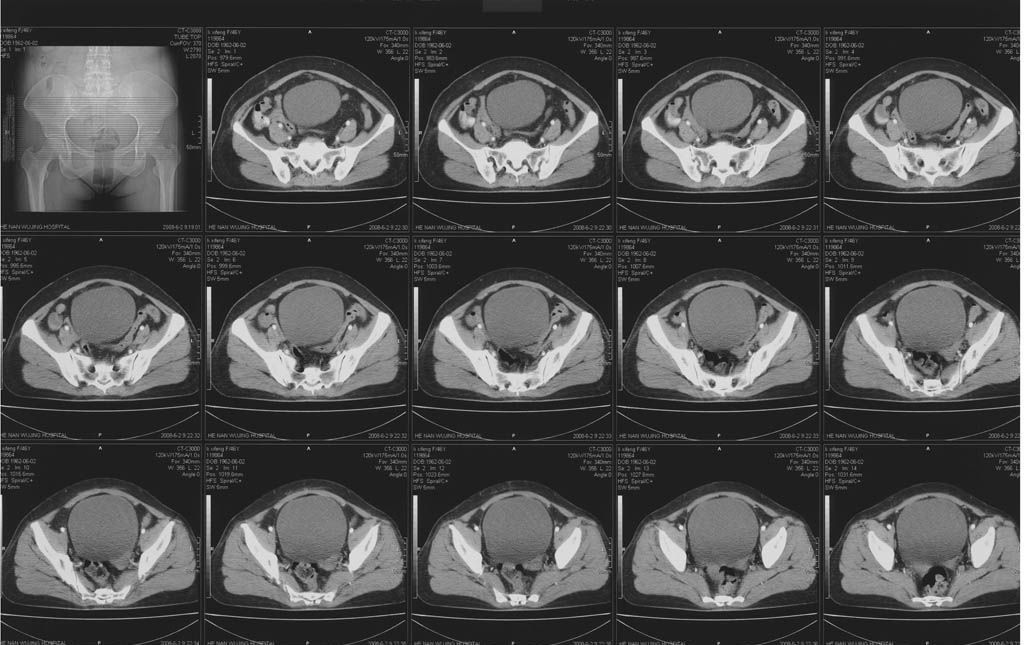

5年前子宫肌瘤 子宫切除,2年前整个下腹痛2周余病因不名,2008年5月底再次左下腹痛行ct,6月2日ct增强,请指教

不知道子宫切除术式是怎么样的?我看宫颈是健全的,子宫体下部部分残留,应该属于次全切吧?

我考虑是位于残留子宫体部的左侧又重新复发了一个肌瘤,中间似有坏死,b超或者彩超进一步检查吧!

次全切除!子宫肌瘤复发。

后面的图像就是增强的啊,包块下部还有细小的钙化点